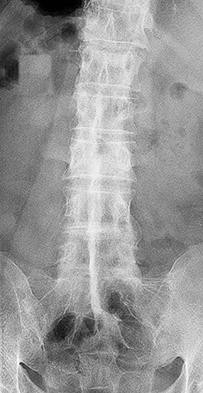

A 65-year-old female presents with progressive stooped posture, early satiety, and severe low back pain. Radiographs reveal degenerative adult spinal deformity.

Which of the following spinopelvic parameters is most strongly correlated with poorer health-related quality of life (HRQOL) outcomes if it exceeds normative thresholds?